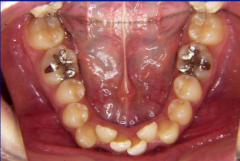

ステップ5.精密検査

口腔内写真,レントゲン

(必要に応じてCT)

印象(歯型)採得

装置装着前